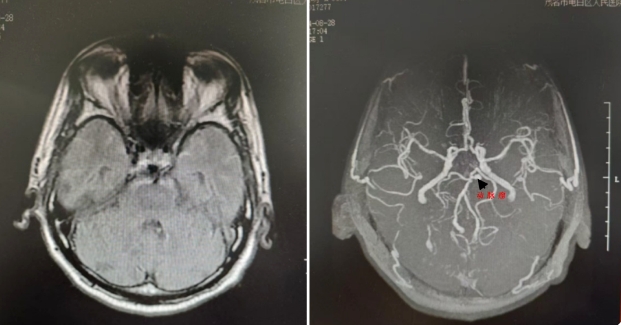

患者楊伯伯因“持續(xù)頭暈6年,加重1天”于2024年8月27日入住我院神經(jīng)內(nèi)科。入院后,經(jīng)過磁共振成像檢查,朱紅星主任和吳厚成副主任醫(yī)師對影像資料進(jìn)行了細(xì)致分析,結(jié)合患者病史和體檢結(jié)果,高度懷疑患者左側(cè)大腦后動(dòng)脈起始部存在動(dòng)脈瘤,并伴有蛛網(wǎng)膜下腔出血的可能。隨后,神經(jīng)外科梁海波副主任受邀會診,經(jīng)過神經(jīng)內(nèi)外科的聯(lián)合評估,楊伯伯被迅速轉(zhuǎn)至神經(jīng)外科。